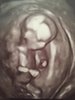

Niestety wyrostka na tym zdjęciu nie wiedze, choć bokiem, bo nóżka zasłania... Musisz poczekać na potwierdzenie płci